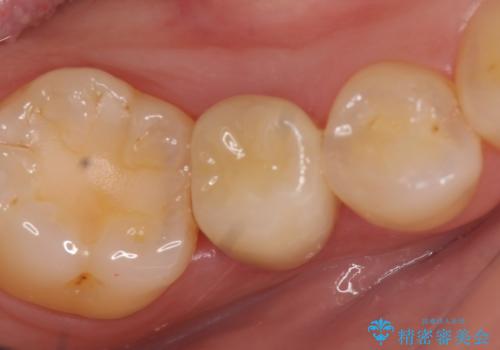

奥歯の虫歯 オールセラミッククラウンによる補綴治療